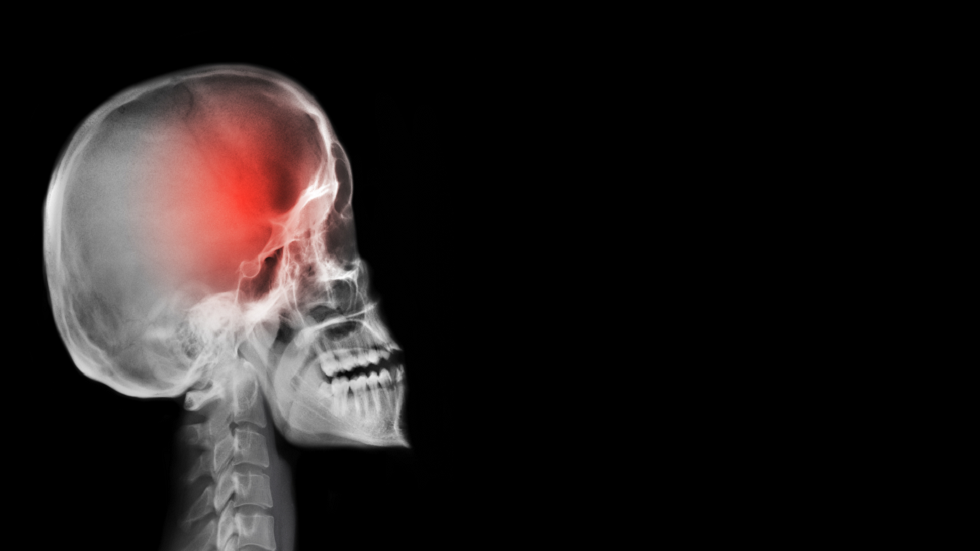

أعراض يومية شائعة قد تكون مؤشرات على أورام الدماغ

حذرت باحثتان من جامعة كوين ماري في لندن من أعراض يومية شائعة غالبا ما تُهمل "قد تكون في بعض الحالات علامات مبكرة على ورم في الدماغ".

وأجرت كل من لورا ستاندن، طالبة دكتوراه، وسوزان سكوت، أستاذة جامعية، مقابلات مع مرضى شُخصوا بأورام دماغية، ووجدتا أن هناك نمطا متكررا من تجاهل الأعراض المبكرة من قبل المرضى والأطباء العامين على حد سواء، ما يؤدي إلى تأخير التشخيص.

أكدت الباحثتان أن الكشف المبكر عن أورام الدماغ أمر بالغ الأهمية لتحسين فرص النجاة، حيث لا يعيش سوى ربع المصابين بأورام الدماغ في مراحلها المتأخرة أكثر من عام.

وتشمل العلامات التي تستدعي الانتباه لها:

صعوبة إيجاد الكلمات أو تكوين الجمل، ما يعطل المشاركة في المحادثات اليومية.

ضبابية الدماغ، أي صعوبة في التركيز أو التفكير بوضوح أو تذكر المعلومات.

خدر ووخز في أجزاء من الجسم، أحيانا يظهر في جانب واحد فقط.

اضطرابات الرؤية، مثل ازدواج الرؤية أو رؤية الخطوط منحنية.

الكتابة الفوضوية أو فقدان التنسيق بين اليد والعين.

تغيرات في الشخصية أو المزاج، قد تكون خفية لكنها ملحوظة.

الصداع المزمن المستمر أو المتكرر.

وأوضحت الباحثتان أن تكرار الأعراض أو ظهورها مجتمعة، حتى لو بدا أنها مرتبطة بالتوتر أو التعب، يستدعي تقييما طبيا عاجلا.

روى المرضى شعورهم بالغموض وعدم القدرة على التعبير عما يشعرون به عند ظهور صعوبة في تكوين الجمل، وضبابية الذهن وخدر أو وخز في الوجه والجسم، إضافة إلى مشاكل في الكتابة والتنسيق الحركي. وأوضحت الباحثتان أن الأعراض غالبا ما تُنسب للتعب أو التوتر، لكنها قد تكون مؤشرا على ورم دماغي إذا استمرت.

أبحاث حديثة للكشف المبكر

تعمل الباحثتان على تطوير أدوات تساعد الأطباء العامين على اكتشاف أورام الدماغ مبكرا، عبر اختبارات للوظائف الإدراكية لتقييم الذاكرة ومهارات اللغة، وخزعات سائلة للكشف عن أجزاء من الحمض النووي للورم في الدم.